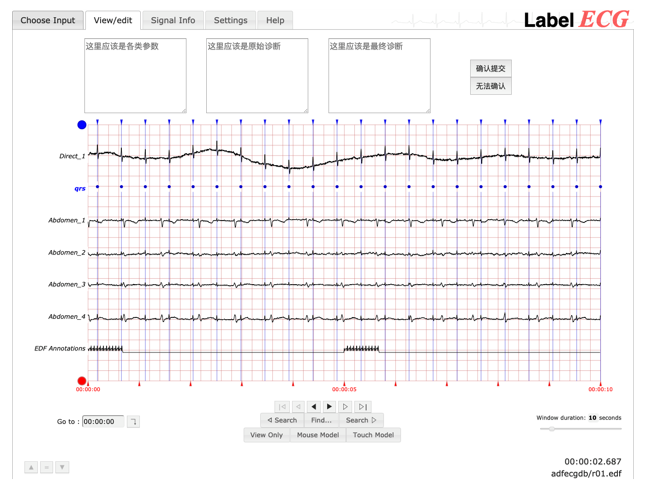

二、构建了心电图的分布式标注工具LabelECG。LabelECG 是一个在线分布式心电标注工具。医生可以通过台式机、笔记本电脑、平板电脑甚至手机上的网络浏览器访问 LabelECG。LabelECG 更易于部署和负责的数据管理性能,使医生可以忽略对数据的操作,专注于心电图的标注。LabelECG 能够帮助用户上传、可视化、注释和修改他们的心电图记录。

LabelECG:心电的分布式标注工具